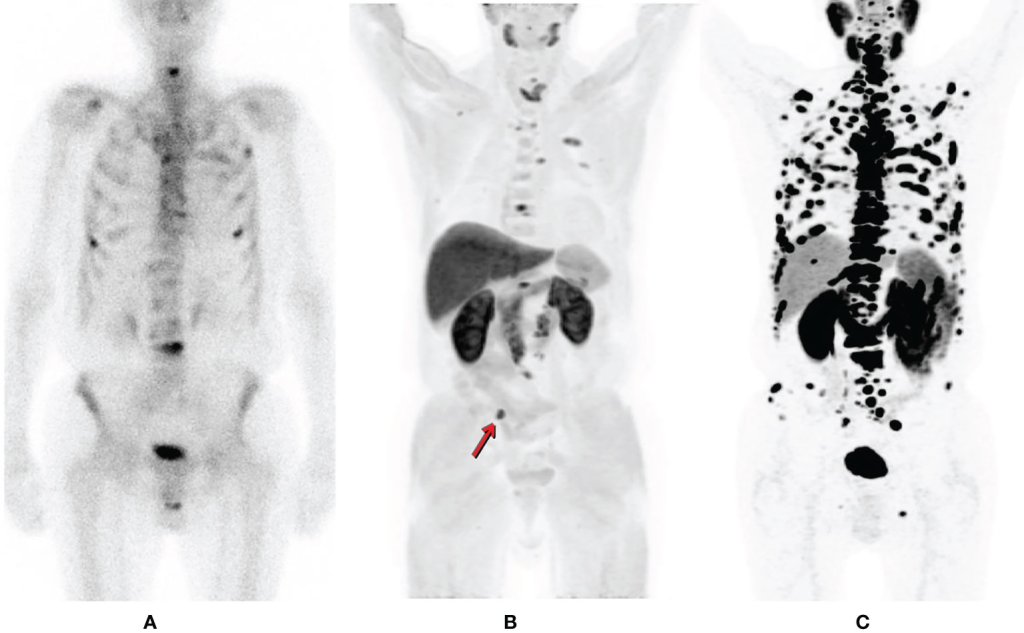

PET-CT com PSMA: revolução no diagnóstico e tratamento do câncer de próstata

Por Sumara Abdo Lacerda Matedi, médica nuclear, e Marcos Villela Pedras Polonia, médico e executivo, via Brazil Health* 29 jul 2025, 17h30 | Atualizado em 30 jul 2025, 10h45